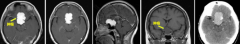

53岁的李阿姨一直有慢性头痛的病史,刚开始一家人都以为这只是个头疼脑热的小毛病,直到有一天,李阿姨因突发癫痫送医,结果被查出大脑左额凸面及前段大脑镰旁有肿瘤占位,于...